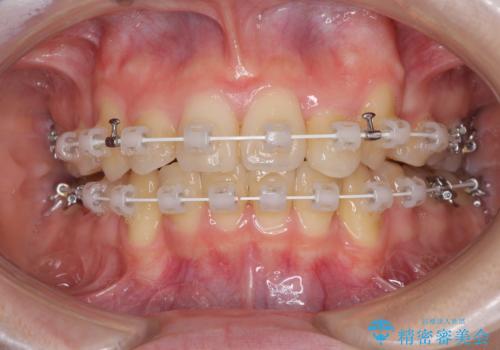

- 審美装置

- 2年10ヶ月

- 10-30回

結婚式の予定があったため、まずは前歯をきれいに整えるようにしました。

結婚式の時には一時的に前歯の装置を外し、口元を気にせず笑える結婚式を迎えることができました。

その後スペースを閉じるために時間を要しましたが、満足のいく仕上がりとなりました。